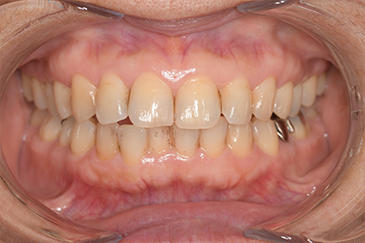

CASE 4

Before

After

基本情報

| 年齢・性別 | 52歳・女性 |

| 主訴 | クリーニングしたい |

| 治療内容 | スケーリング・PMTC |

| 治療期間 | 60分 |

| 治療費 | 約7,000円 |

| リスク・副作用 | 知覚過敏、歯肉退縮 |

| 治療方針 | 歯石とステインを除去して、今後は定期検診でのクリーニングと併せてガムピーリングやホワイトニングを行います。 |

| 担当者所見 | 歯肉の色素沈着が目立つため、ガムピーリングを行いながらホワイトニングを行うことをおすすめします。 |